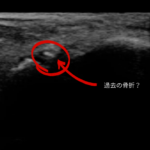

この前、妻が「外くるぶしが少し痛い」というので超音波エコーで観察しました。 すると外くるぶしの前方に不正象が、、、 恐らく子どものころに足首を骨折してそのまま大きくなってしまった骨折のかけらのようなものだと思います。 実は、 「少しひねっただけだから大丈夫」 「歩けているから捻挫だと思う」 10歳以下のお子さんの場合、 実は捻挫より骨折の方が多いことをご存じ……続きを読む